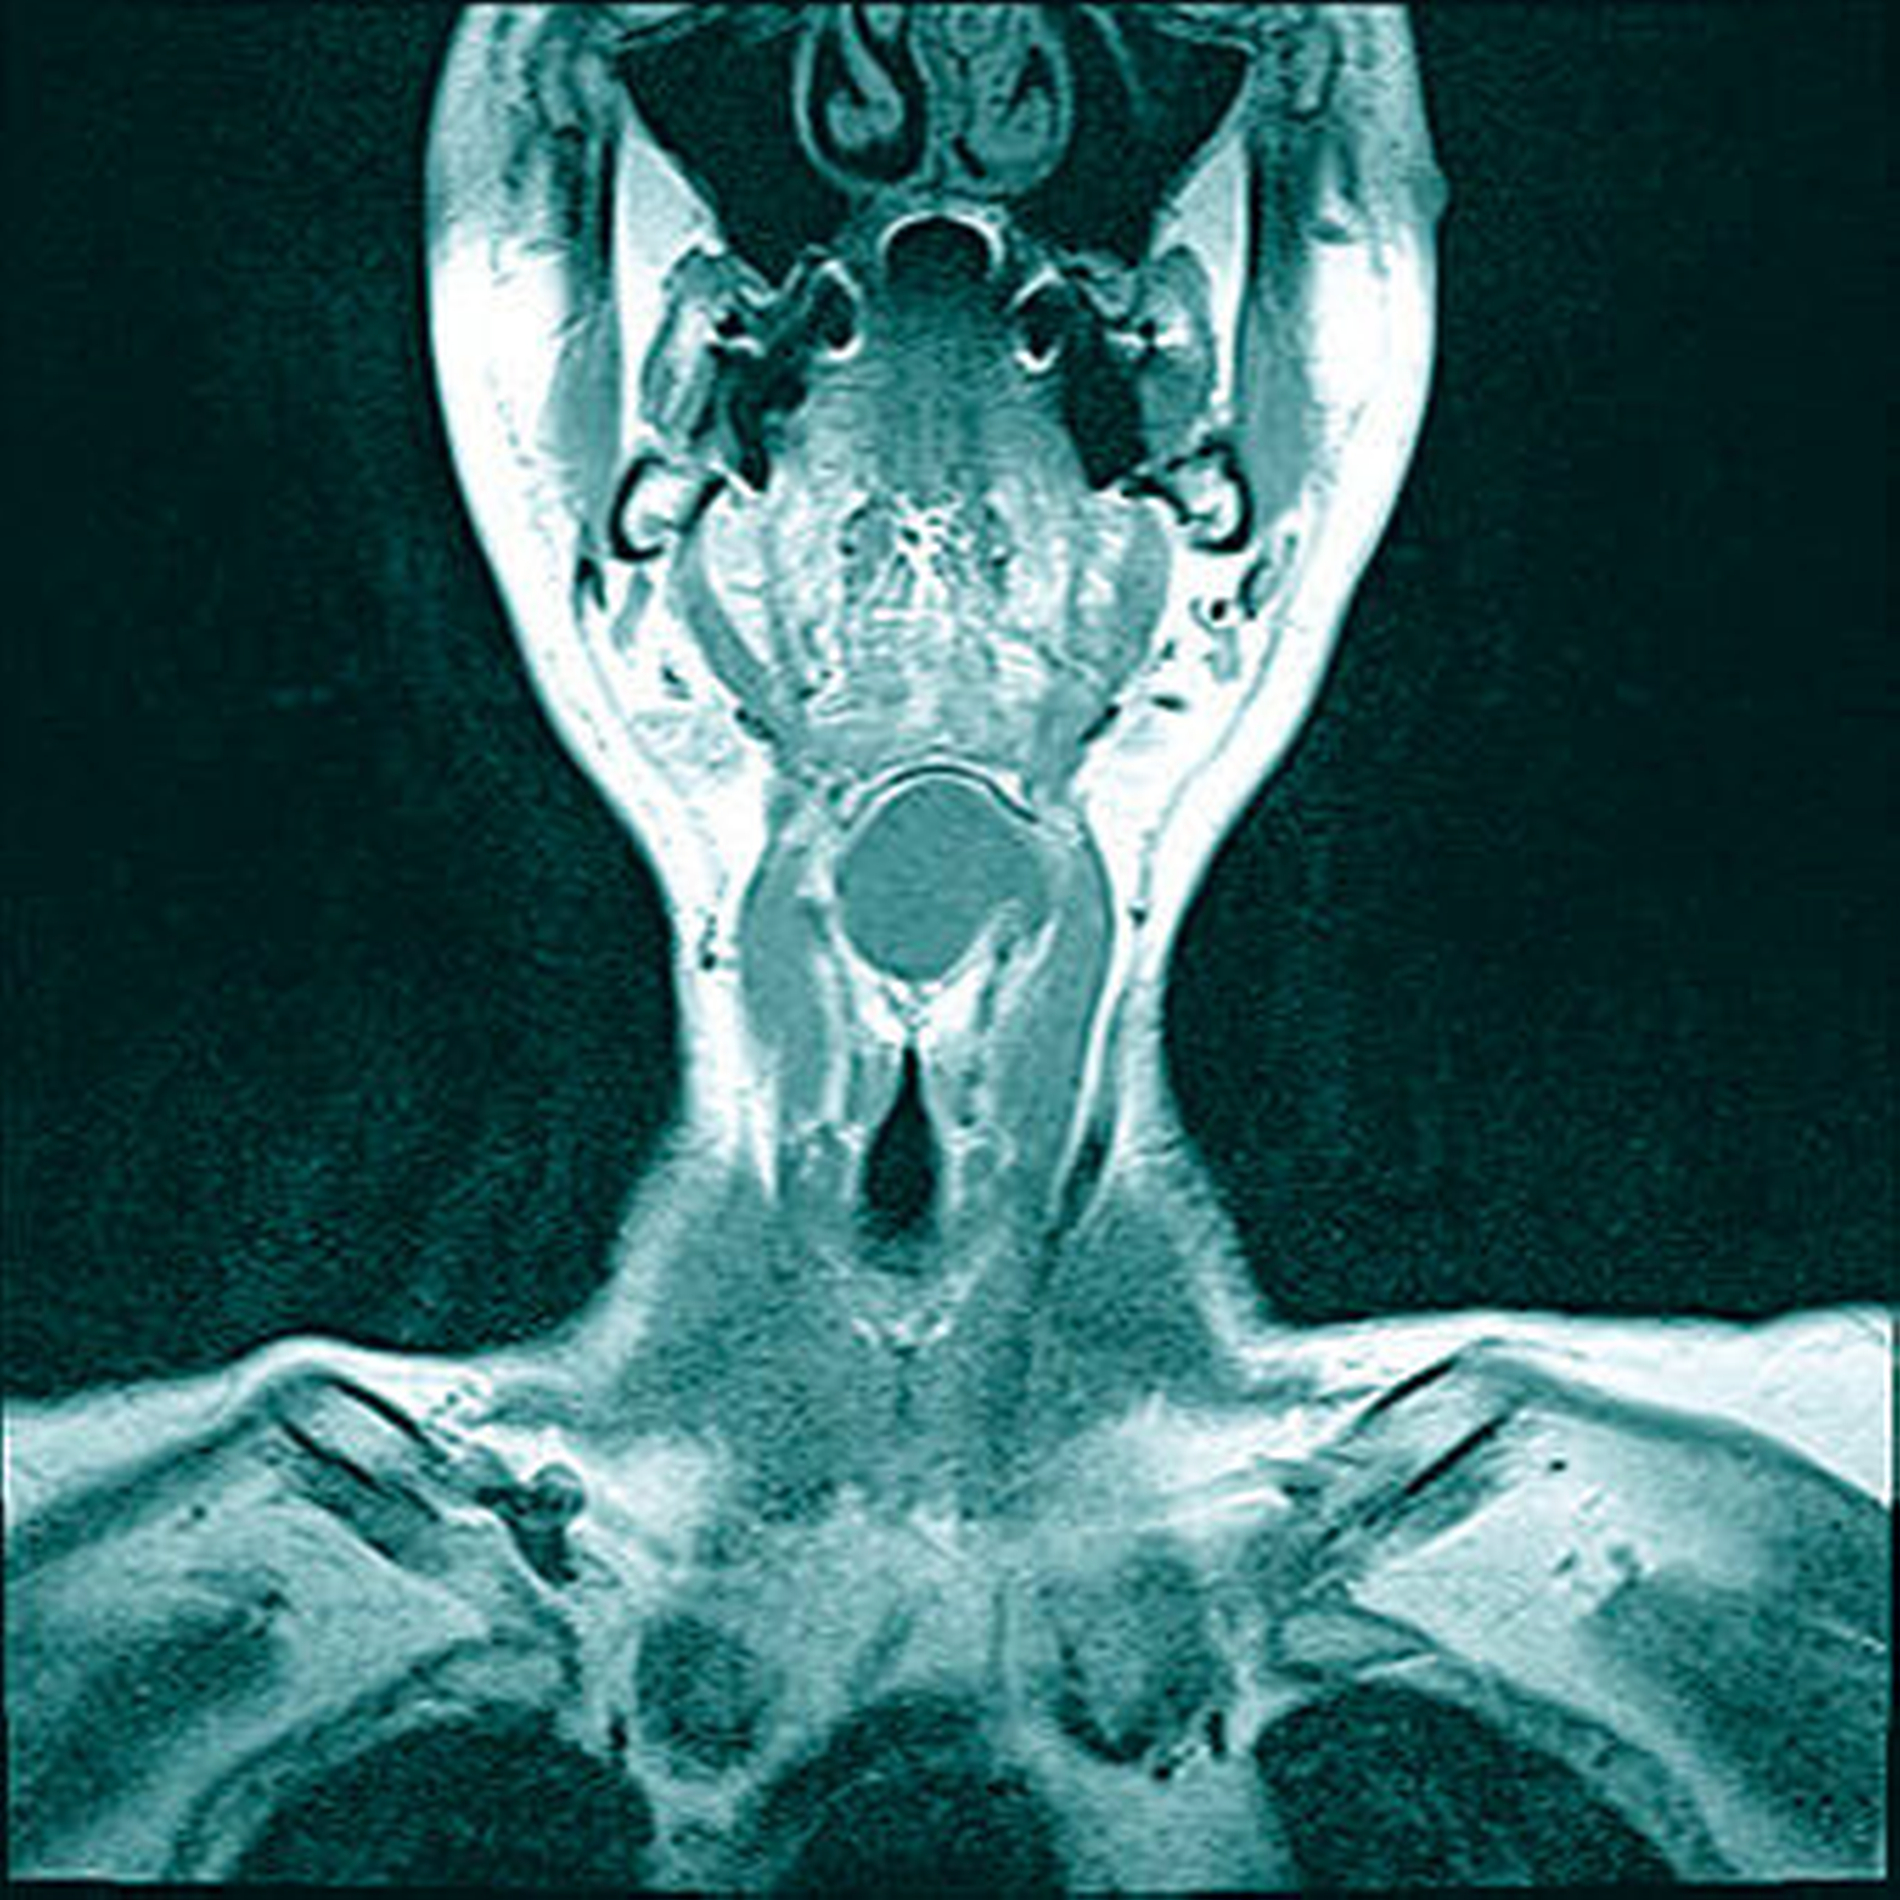

Die unter ambulanten Bedingungen angefertigte schnittbildgebende MRT-Untersuchung des Halses zeigte eine 41×35×27 mm große, gut abgrenzbare und abgekapselte Raumforderung mit homogener Binnenstruktur. Die Dichtewertmessung wies anhand der Verteilung der Hounsfield-Einheiten einen mit flüssigkeitsäquivalentem Gewebe, gefüllten Hohlraum auf (Abbildung 2a). Dieser war mit einer mittigen Einschnürung in der Medianebene des Halses und in der Mitte des Os hyoideum lokalisiert (Abbildung 2b). Dabei werden die Verdrängung des aerodigestiven, benachbarten Raumes sowie die Anhebung des Mundbodens und der Zungengrundmuskulatur deutlich (Abbildung 2c).